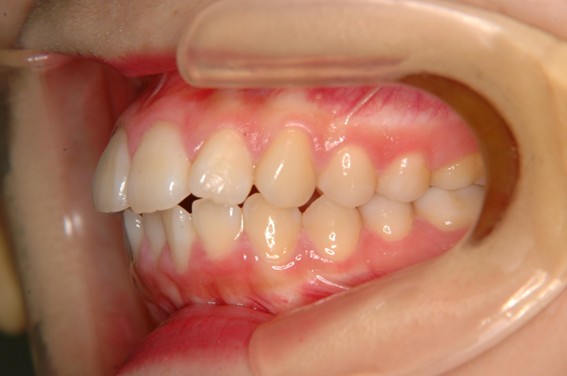

| 主訴 | 口元がでている、口が閉じずらい、上の歯と下の歯のがたつき、顎がない。 |

| 治療内容 | 上下のワイヤー矯正を行いました。 |

以前骨切りを勧められたことがあるという方でしたが、抜歯矯正で口元の突出や顎のしわを改善しました。上唇の厚みや頬の高さを考慮し、老けた印象にならないよう配慮。お顔全体のバランスと年齢に合わせた治療を行いました。